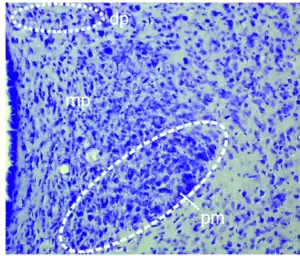

Núcleos neuronales

Los cuerpos de las neuronas hipotalámicas están agrupados en núcleos, los cuales disponen de proyecciones axonales con las que alcanzan otras regiones del encéfalo y otros núcleos hipotalámicos. Tal disposición permite la continua comunicación entre las neuronas del hipotálamo y otras áreas del cerebro.[36]

Desde el punto de vista anatómico el hipotálamo se divide en tres zonas principales: medial, lateral y periventricular. Los núcleos se concentran en las zonas medial y periventricular, las más relacionadas con la regulación central endocrina. A la zona lateral se le considera un «relevo» donde están establecidas conexiones del hipotálamo con los elementos encefálicos más rostrales.[37]

Son once los núcleos principales del hipotálamo y sus funciones permiten la «integración de las funciones del cuerpo para el mantenimiento de la homeostasis».[38]